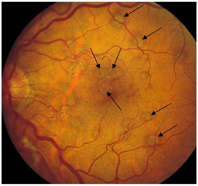

视盘的评估

与此同时,以下视神经盘的评估可帮助患者发现其他暂无症状、但有健康风险的疾病,如早期青光眼或脑肿瘤。这可能会帮助挽救患者的健康和生命。

- 视盘的边界;

- 视盘的颜色;

- 杯盘比:视杯纵轴长度和视盘纵轴长度的比值(十分位比值);

- 盘沿出血;

- 局限性视神经纤维束缺失。

▲ 视杯扩大:图中大视杯的杯盘比达到了7/10或0.7

▲ 局限性视神经纤维束缺失